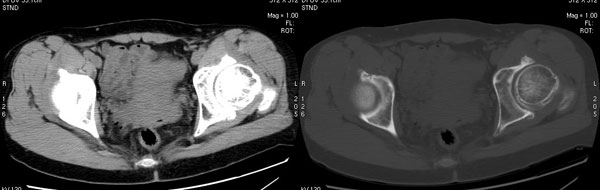

以下是引用jiajie在2006-7-14 17:19:00的发言:[br]ct所见:双侧髋关节不对称,左侧关节间隙变窄,关节面毛糙。左侧股骨头变形、无明显变小,前上缘与髋臼融合,融合处骨质明显增生硬化,并见数个小囊变影。股骨头下端与股骨颈交界部见囊样变,邻近肌肉内见囊样密度减低区,ct值24hu。右侧髋关节形态未见异常。[br][br]ct诊断:左侧髋关节结核可能,请结合临床资料进一步分析。

以下是引用lihuuuu在2006-12-5 10:14:00的发言:[br]定位像示:左侧髋臼变浅,倾斜度加大,髋臼外上缘呈波浪状不规则,骨质增生硬化,髋关节上缘间隙明显变窄,股骨头向外上轻度移位。轴位像示:左侧股骨头变形,前上缘与髋臼融合,融合处骨质明显增生硬化,并见数个小囊变影。股骨头下端与股骨颈交界部见囊样变,邻近肌肉内见密度减低区,ct值24hu,内缘见弧形高密度钙化影。右侧髋关节形态未见异常。[br]ct诊断:左侧髋臼发育不良[br] 左侧股骨头缺血性坏死[br] 左侧肌肉内低密度影伴有高密度钙化-考虑早期骨化性肌炎[br] [br]“我认为在描述上已经写了肌肉部分,印象诊断里应该写主见”[br]